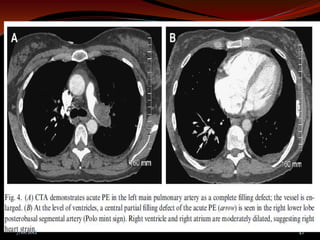

CT Angiogram

 Benefits                  Limitations

 Available             IV contrast

 Direct image          Expensive

 Alternative Dx        Patient

 Pelvic/leg veins       cooperation

 Uncertain

sens/spec

 “CT should not be used alone for

suspected PE, but combining tests

improves accuracy and reduces need for

angiography”